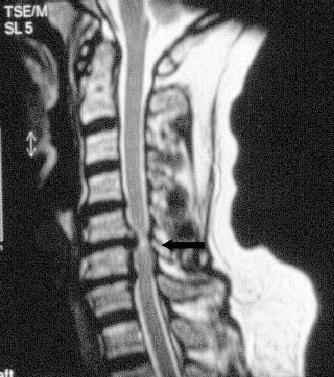

Halswirbelsäule

Zumeist ist eine Kernspintomographie ausreichend. Bei Verdacht auf Rückenmarksschaden ist zusätzlich eine elektrophysiologische Untersuchung der Nervenleitung erforderlich.